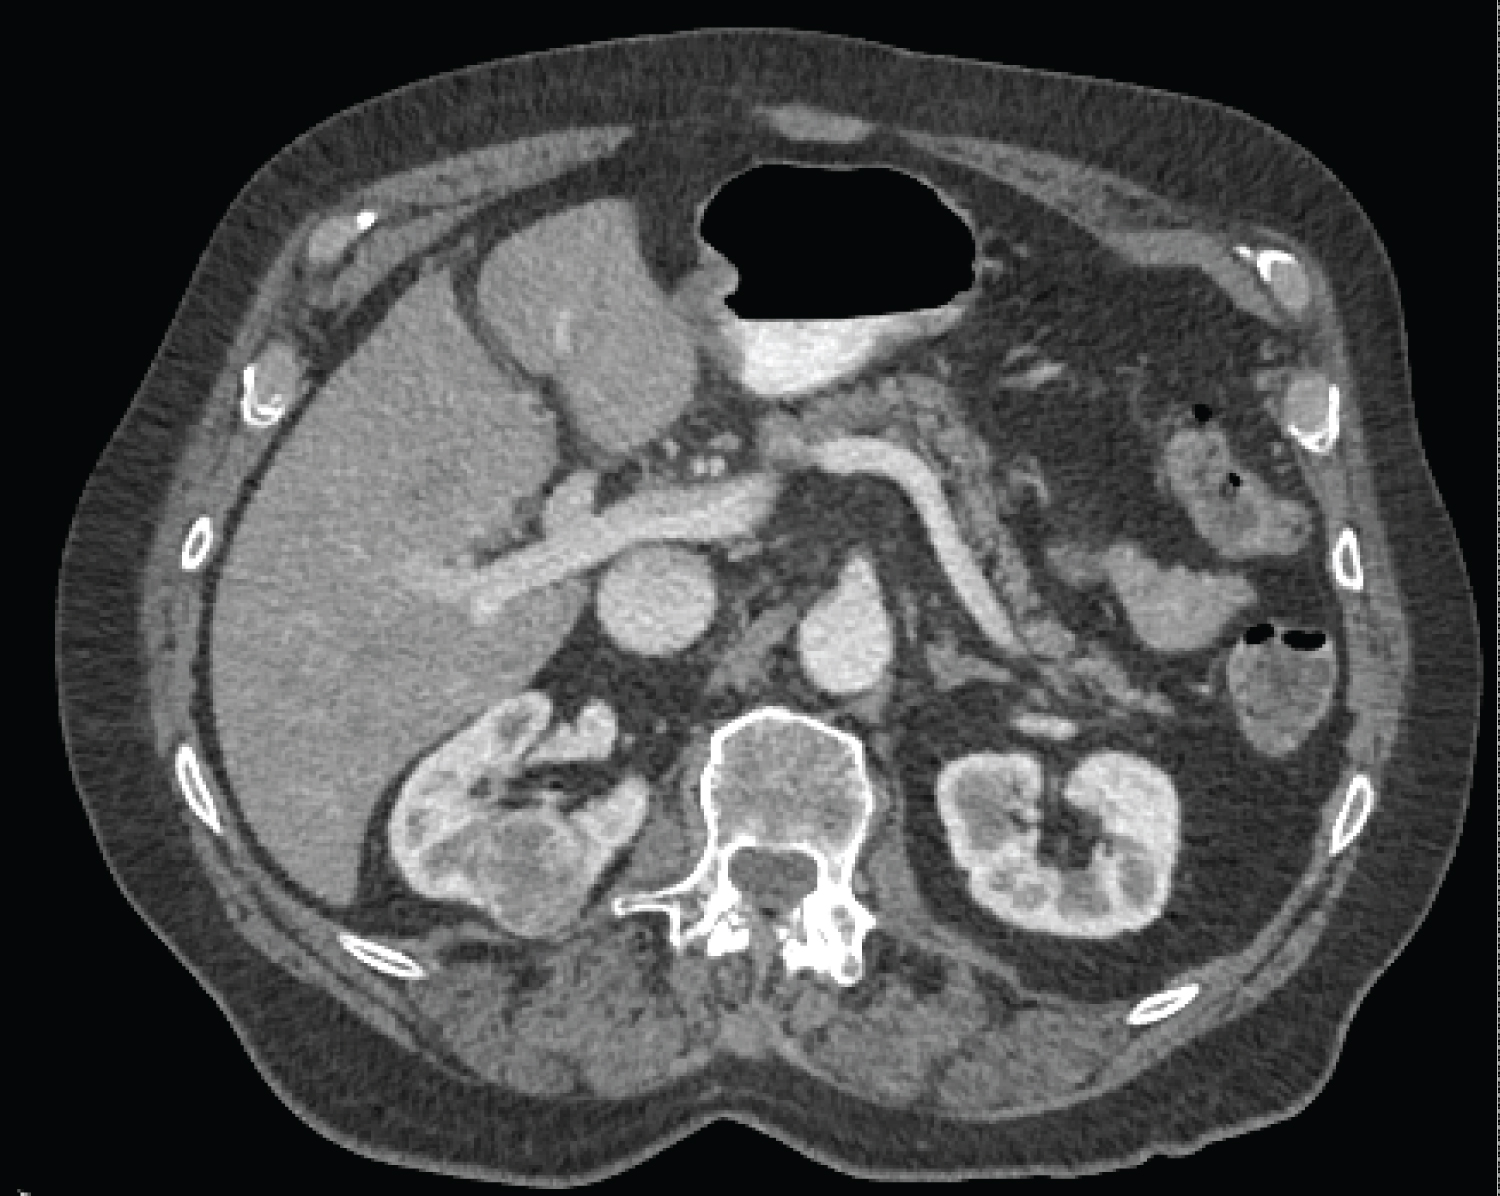

An 83-year-old male who presented with a growing right-sided mass, previously biopsied and shown to be an oncocytoma (Figure 1). Given the growth from 2.8 cm to 3.6 cm over 8 months, there was concern for sampling error and after multidisciplinary discussion percutaneous ablation was pursued. The patient underwent MWA of the 2.9 × 3.6 cm utilizing 3 probes at 90W for 10 minutes (Long Perseon Microthermx®) with an expected ablation zone of 4 × 5.3 cm (Figure 2). Three months after the ablation, the patient developed shortness of breath secondary to a pleural effusion and presented to OSH where he underwent multiple thoracenteses. Given the refractory nature of his effusions, he underwent placement of a tunneled pleural catheter for management of this high volume, refractory effusion. At the time of placement of this tube, urinothorax was considered as an etiology of this effusion and a sample was sent for fluid creatinine, which was 52 mg/dl (concurrent serum creatinine was 0.8 mg/dl). An excretory phase CT demonstrated accumulation of contrast in the chest, confirming the diagnosis of with urinothorax (Figure 3). A percutaneous nephroureteral (PCNU) tube was then placed for urinary diversion and output from the chest tube abated. One month later, the PCNU was removed at outside hospital with subsequent recurrence of the urinothorax. Owing to significant morbidity and frustration the patient opted to undergo right nephrectomy rather than additional stenting.

Figure 1: 2.9 × 3.6 cm right renal mass, previously biopsied and shown to be an oncocytoma. Given interval growth, concern was for sampling error and simultaneous biopsy and ablation was planned. View Figure 1